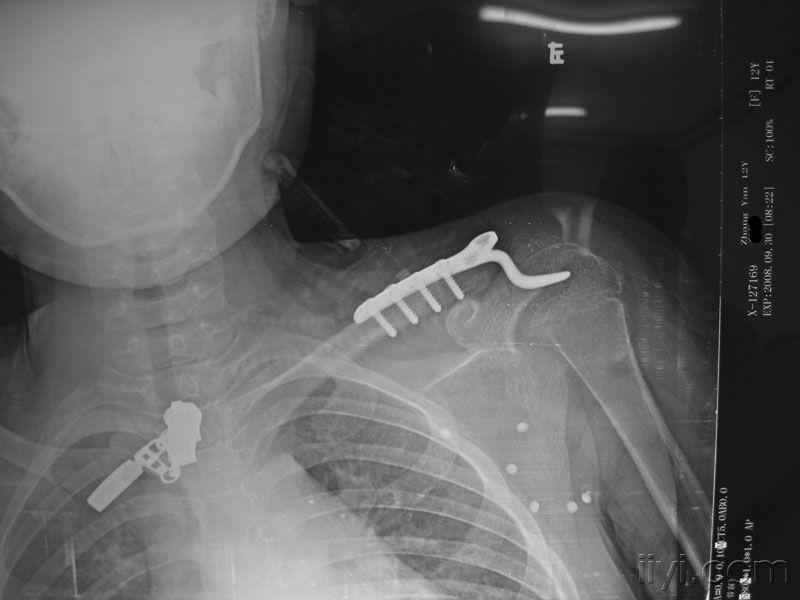

儿童左锁骨远端骨折一例